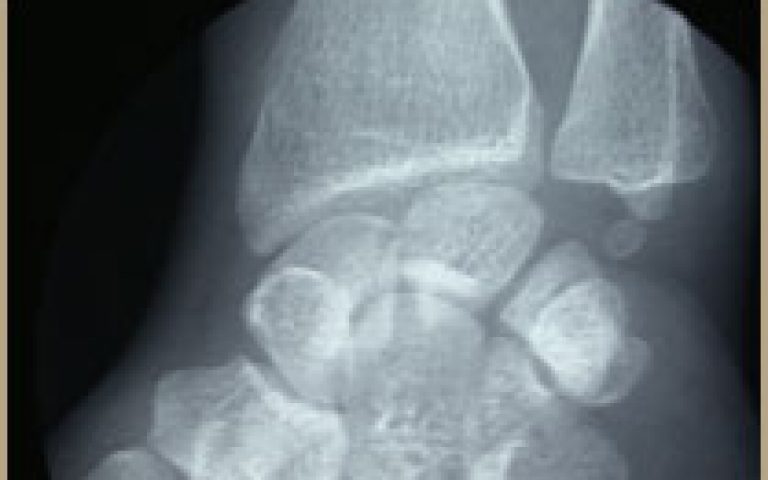

Pathologies de la Main et du poignet Arthrose post-traumatique

Arthrose post-traumatique

Pathologies de la Main et du poignet Pseudarthroses du scaphoïde

Pseudarthroses du scaphoïde

Pathologies de la Main et du poignet Maladie de Kienbock

Maladie de Kienbock

Pathologies de la Main et du poignet Maladie de Preiser

Maladie de Preiser